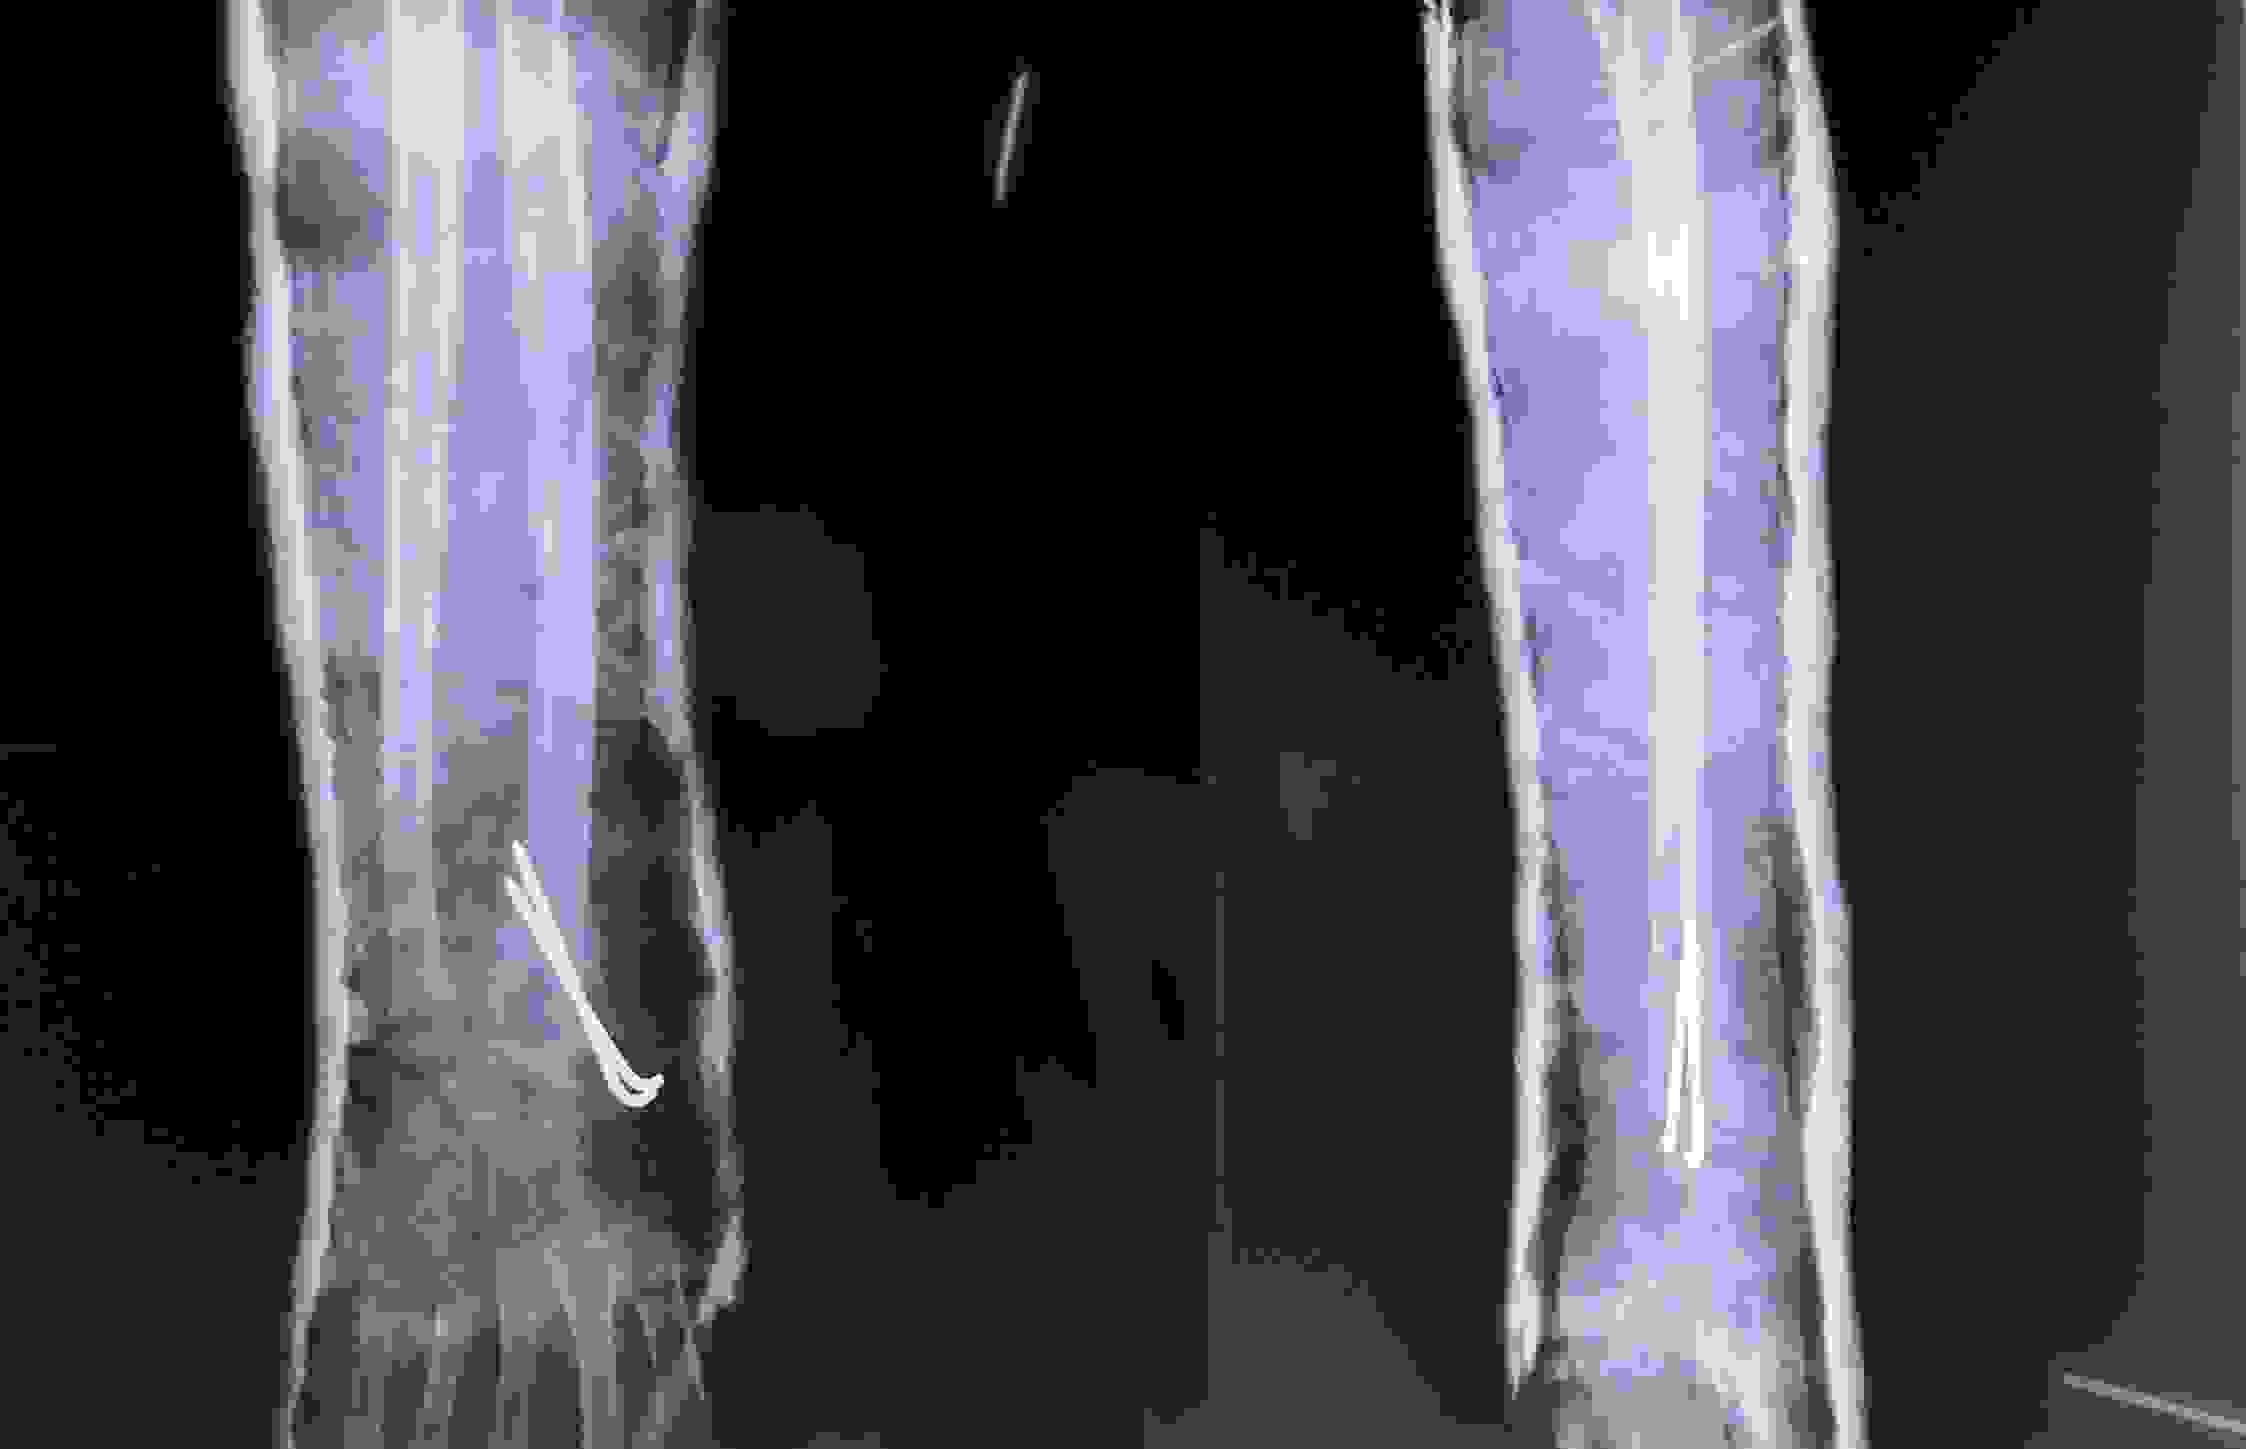

Co rút Dupuytren là bệnh gây ra các nốt sần, cục u hoặc bướu nhỏ dưới da ngón tay và lòng bàn tay, thường ảnh hưởng tới các ngón thứ tư và thứ năm. Bệnh nhân có thể thấy cảm giác bó chặt các ngón bị bệnh đến nỗi khó duỗi, đôi khi có tăng cảm giác đau. Một số trường hợp, sự co thắt này làm ảnh hưởng nặng đến chức năng và vấn đề thẩm mĩ, song hầu hết bệnh nhân chịu đựng tốt bởi vì sự co thắt xuất hiện ở trạng thái chức năng bình thường của bàn tay.